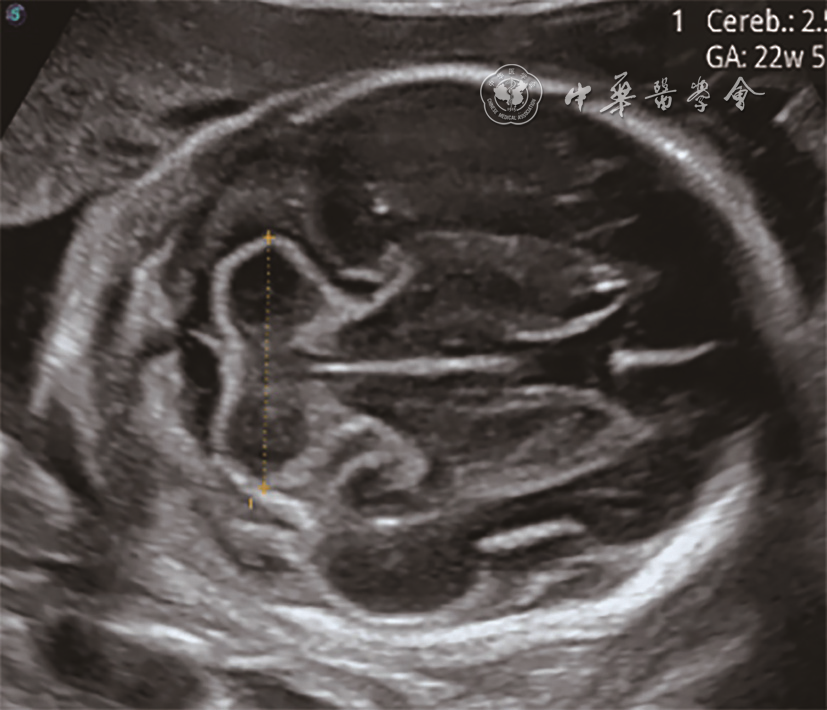

1. 产前超声检查:与正常胎儿小脑图像比较(图1),6例胎儿小脑横切面声像图示小脑形态均失常,左右不对称,一侧小脑减小,形态失常,伴或不伴蚓部异常,对侧小脑半球大小、形态正常(图23);其中4例小脑蚓部发育不全或发育不良,1例合并蛛网膜囊肿,1例合并神经元移行障碍和胼胝体发育不全。产前超声诊断:左侧小脑发育不全4例,右侧小脑发育不全2例。

图1 中孕期正常胎儿小脑超声表现:左右小脑半球对称,边界规则